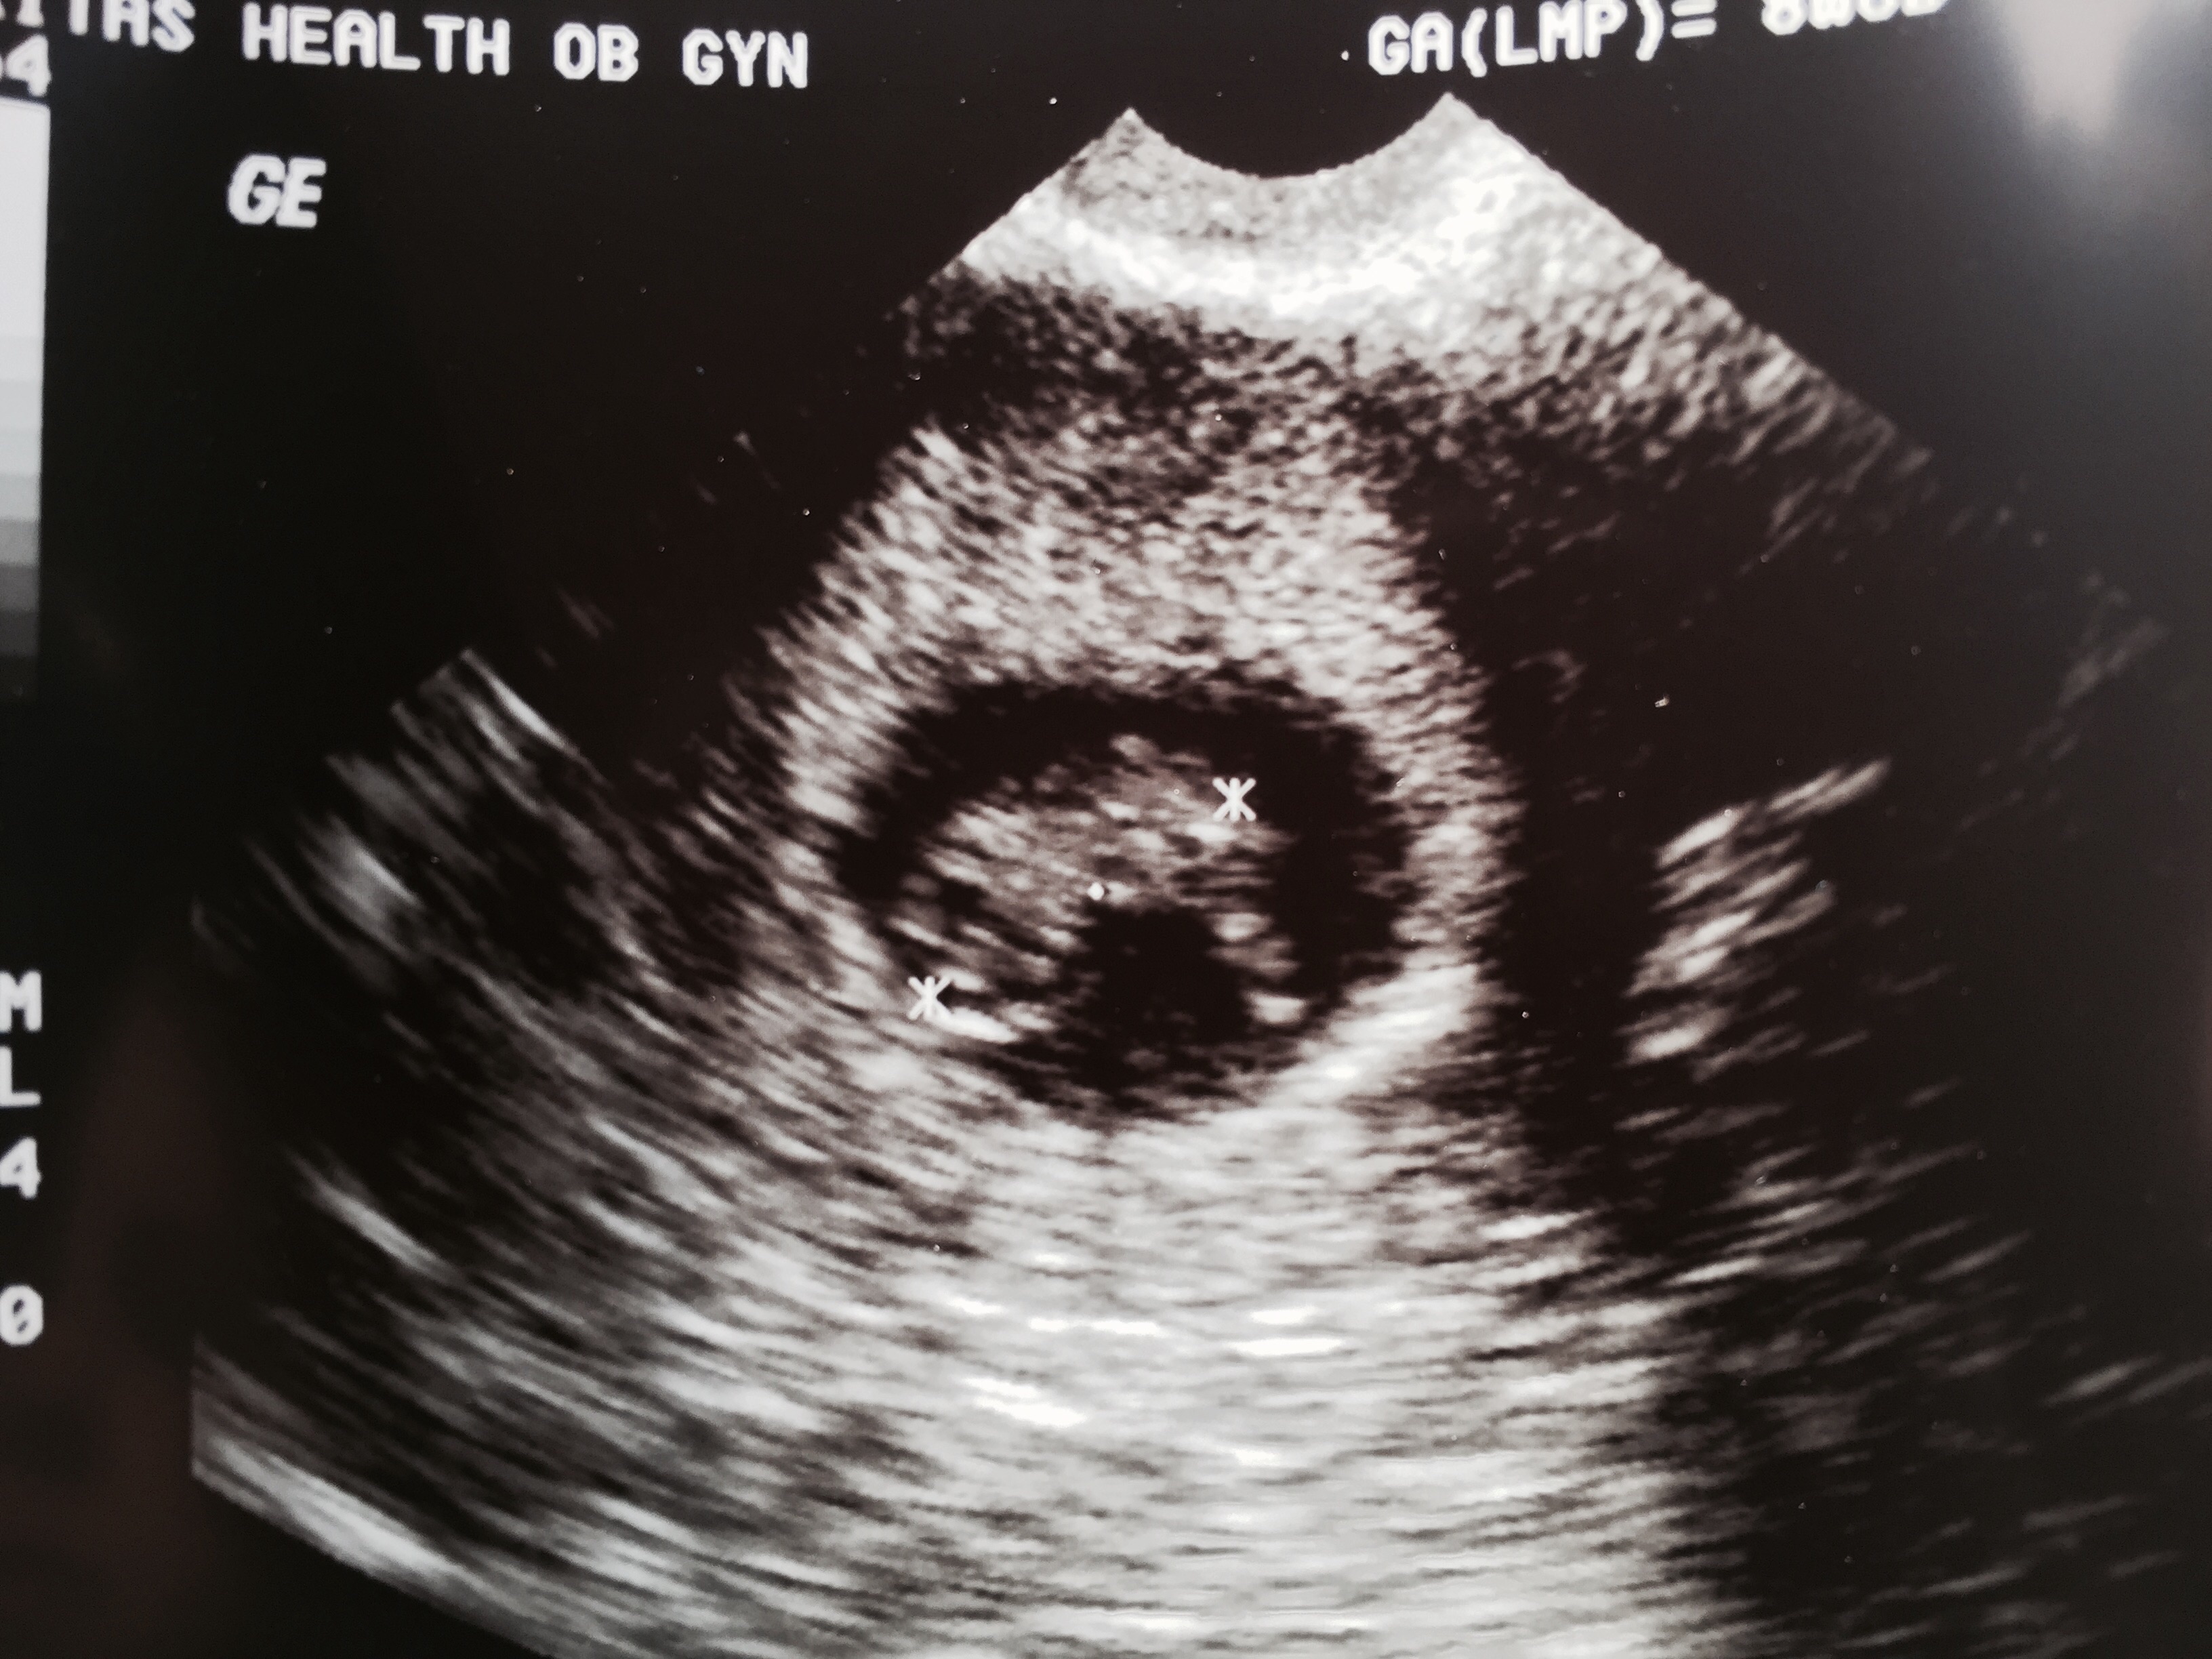

I had my first ultrasound last Wednesday. I went in thinking I was 9weeks 6days (this was based off my last cycle) but after they measured the baby they said I was 10weeks 6 days. I can't stop looking at my baby. I'm a FTM also.